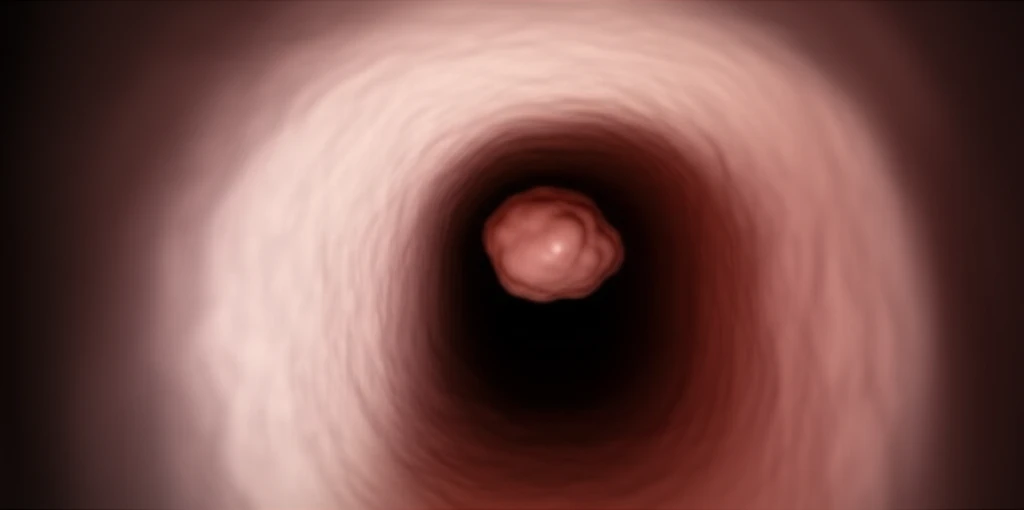

조직검사 및 용종 제거 후의 관리 (1~2주간)